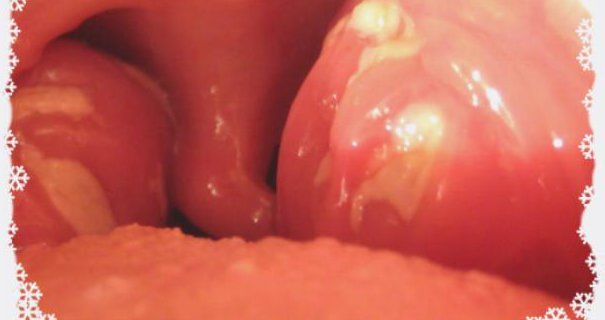

Так выглядит фолликулярная ангина.

Гной в фолликулах серо-желтого цвета, они усеивают область поражения и при визуальном осмотре хорошо видны.